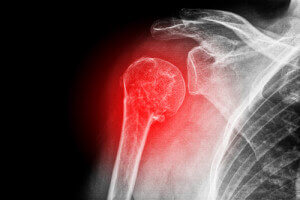

Механизм разлома головки плеча

Прямое нарушение целостности костной ткани ─ следствие удара по наружной поверхности руки, плечевого сустава. Косвенное воздействие на головку кости случается в результате падения с опорой на плечо, лопатку, спину, руку, отведенную в сторону в локтевом суставе.

Головка полностью отходит от диафиза (тело кости). Ее смещение при тяжелой травме бывает существенным, вплоть до того, что переворот происходит на 180°, хрящевой стороной к шейке плеча. Чаще раскалывается на несколько отломков.

При диагностике перелом головки нужно разграничить от вывиха, ушиба, разлома бугорков, анатомической шейки, лопатки, суставной впадины. Вид травмы определяют на основе рентгеновского исследования.